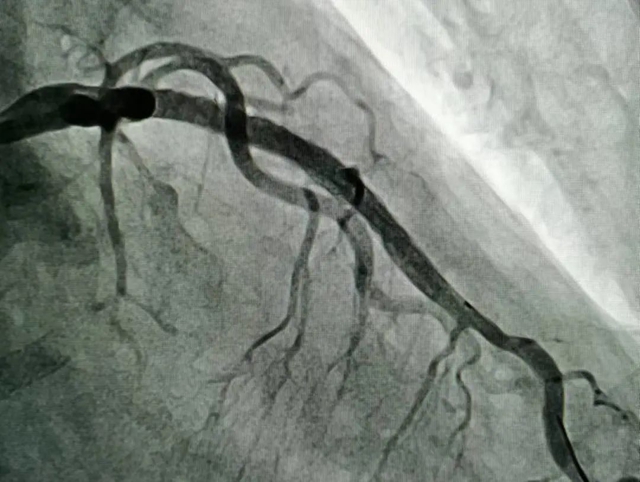

前降支植入支架后

一切准备就绪后,潘洪教授带领李文龙主治医师及杨廷富主管医师分两次为匡阿姨行冠状动脉介入手术,术后症状完全改善,两次手术共植入4枚支架。